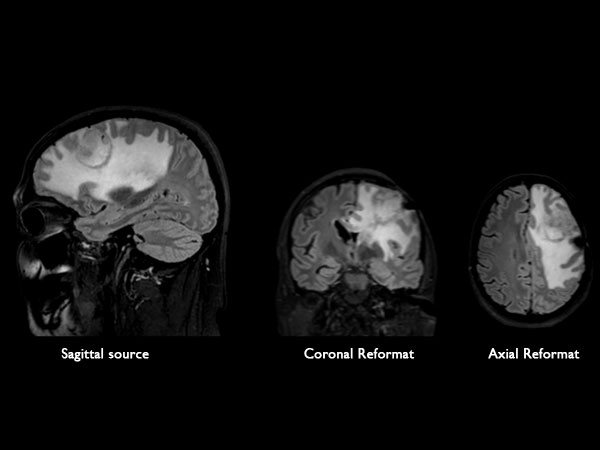

BrainView Flair